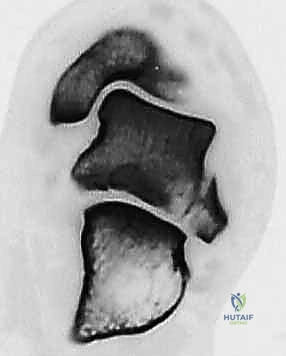

2. التصوير الإشعاعي (الأشعة السينية - X-rays)

هي الخطوة الأولى. تُطلب صور من زوايا متعددة:

* الرؤية الأمامية الخلفية (AP).

* الرؤية الجانبية (Lateral).

* رؤية الهاون (Mortise view).

* رؤية كانال (Canale View): وهي وضعية تصوير خاصة جداً لتقييم عنق الكاحل وتحديد درجة الإزاحة بدقة.

3. التصوير المقطعي المحوسب (CT Scan) - المعيار الذهبي

في عيادة الأستاذ الدكتور محمد هطيف، يُعتبر التصوير المقطعي المحوسب ثلاثي الأبعاد (3D CT Scan) إجراءً روتينياً وحتمياً لأي كسر في عظم الكاحل. توفر الأشعة المقطعية تفاصيل دقيقة للغاية عن خطوط الكسر، مدى التفتت (Comminution)، وحجم الإزاحة المفصلية التي لا يمكن رؤيتها بالأشعة السينية العادية. بناءً على هذه الصور، يقوم الدكتور هطيف ببناء استراتيجية الجراحة (أين سيفتح، ما نوع الشرائح والمسامير التي سيستخدمها، وكيف سيعيد بناء العظم).